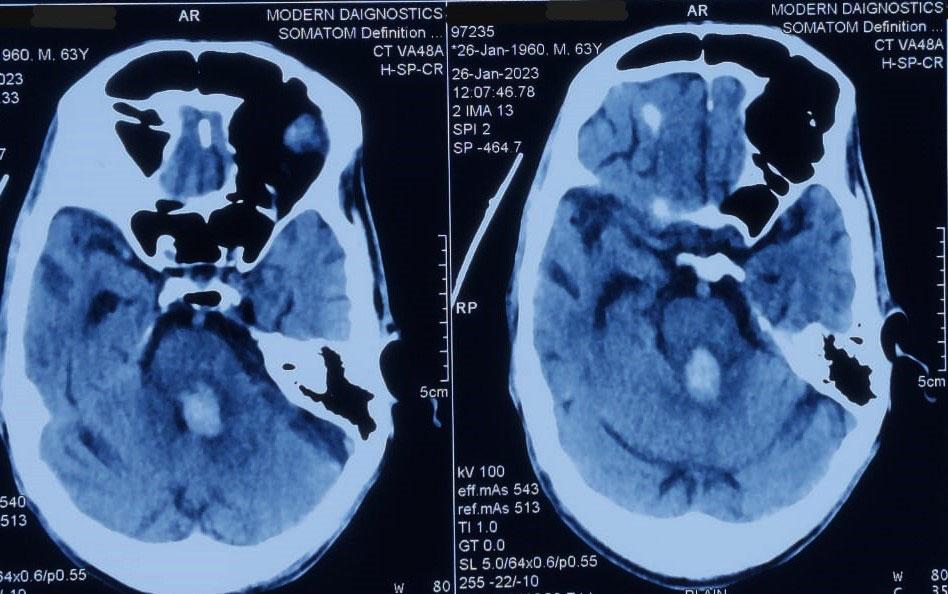

Materials and Methods : This prospective hospital-based study was conducted in the Department of General Surgery, Assam Medical College and Hospital, from January to August 2022. Twenty-five patients diagnosed clinically and radiologically with pancreatic pseudocyst were enrolled. Data on demographics, clinical presentation, etiology, imaging findings, management, and outcomes were collected and analyzed using SPSS v20. Patients were followed up for four months.

Results : Most patients were males (88%) with a mean age of 44.8 years. Alcohol was the predominant etiological factor (72%), and pain abdomen was the universal symptom (100%). Imaging with ultrasonography and CECT abdomen aided diagnosis. Internal drainage was the most common management (40%), followed by external drainage (32%) and conservative treatment (28%). Infection (24%) was the main complication. Recurrence was highest after conservative management.